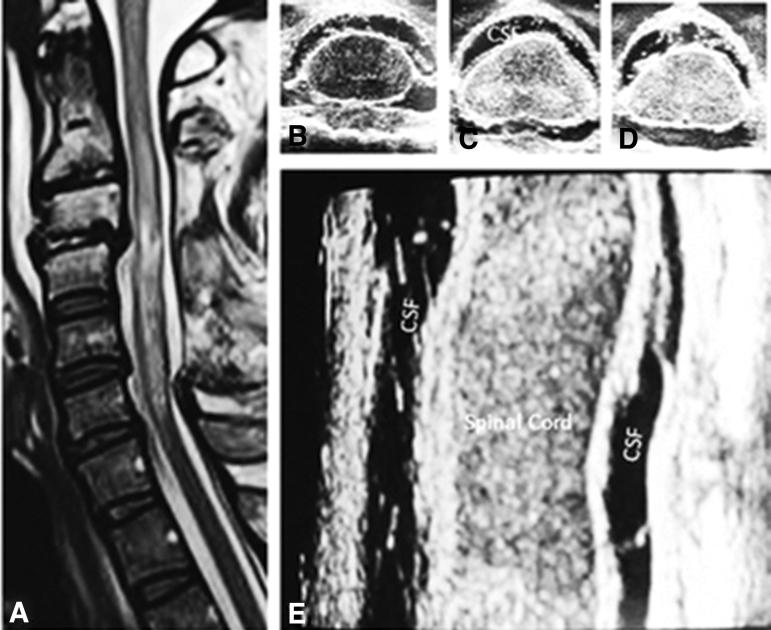

Expansion duraplasty to reopen effaced subarachnoid space and improve spinal cord perfusion, autoregulation, and spinal pressure reactivity index (sPRX) has been advocated in patients with traumatic cervical spinal cord injury (tCSCI). We designed this study to identify candidates for expansion duraplasty, based on the absence of cerebrospinal fluid (CSF) interface around the spinal cord on magnetic resonance imaging (MRI), in the setting of otherwise adequate bony decompression. Over a 61-month period, 104 consecutive American Spinal Injury Association Impairment Scale (AIS) grades A-C patients with tCSCI had post-operative MRI to assess the adequacy of surgical decompression. Their mean age was 53.4 years, and 89% were male. Sixty-one patients had falls, 31 motor vehicle collisions, 11 sport injuries, and one an assault. The AIS grade was A in 56, B in 18, and C in 30 patients. Fifty-four patients had fracture dislocations; there was no evidence of skeletal injury in 50 patients. Mean intramedullary lesion length (IMLL) was 46.9 (standard deviation = 19.4) mm. Median time from injury to decompression was 17 h (interquartile range 15.2 h). After surgery, 94 patients had adequate decompression as judged by the presence of CSF anterior and posterior to the spinal cord, whereas 10 patients had effacement of the subarachnoid space at the injury epicenter. In two patients whose decompression was not definitive and post-operative MRI indicated inadequate decompression, expansion duraplasty was performed. Candidates for expansion duraplasty (i.e., those with inadequate decompression) were significantly younger ( < 0.0001), were AIS grade A ( < 0.0016), had either sport injuries (six patients) or motor vehicle collisions (three patients) ( < 0.0001), had fracture dislocation ( = 0.00016), and had longer IMLL ( = 0.0097). In regression models, patients with sport injuries and inadequate decompression were suitable candidates for expansion duraplasty ( = 0.03). Further, 9.6% of patients failed bony decompression alone and either did (2) or would have (8) benefited from expansion duraplasty.

在创伤性颈脊髓损伤(tCSCI)患者中,提倡进行硬脊膜扩张以重新开放蛛网膜下腔空间并改善脊髓灌注、自动调节和脊髓压力反应指数(sPRX)。我们设计了这项研究,以根据磁共振成像(MRI)上脊髓周围无脑脊液(CSF)界面,来识别需要进行硬脊膜扩张的患者,前提是已经进行了充分的骨性减压。在 61 个月的时间里,104 例连续的美国脊髓损伤协会损伤分级(AIS)A-C 级 tCSCI 患者在术后接受 MRI 检查以评估手术减压的充分性。他们的平均年龄为 53.4 岁,89%为男性。61 例患者因坠落伤,31 例因机动车事故,11 例因运动损伤,1 例因袭击受伤。56 例患者的 AIS 分级为 A,18 例为 B,30 例为 C。54 例患者有骨折脱位;50 例患者无骨骼损伤证据。脊髓内病变长度(IMLL)的平均值为 46.9(标准差=19.4)mm。从损伤到减压的中位时间为 17 小时(四分位间距 15.2 小时)。术后,94 例患者的脊髓前后有脑脊液,判断减压充分,而 10 例患者的蛛网膜下腔在损伤中心处受压。在 2 例减压不充分且术后 MRI 显示减压不充分的患者中,进行了硬脊膜扩张。需要进行硬脊膜扩张的患者(即减压不充分的患者)明显更年轻( <0.0001),AIS 分级为 A( <0.0016),要么是运动损伤(6 例),要么是机动车事故(3 例)( <0.0001),有骨折脱位( = 0.00016),脊髓内病变长度更长( = 0.0097)。在回归模型中,运动损伤和减压不充分的患者是硬脊膜扩张的合适人选( = 0.03)。此外,9.6%的患者单独行骨性减压失败,要么(2 例)要么(8 例)需要行硬脊膜扩张。